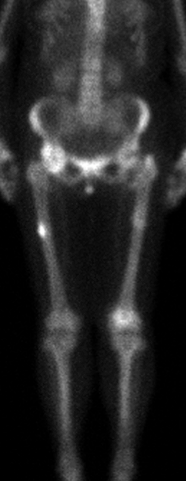

Atypical femoral fractures are rare and atypical thigh-bone fractures that have been associated with anti-osteoporosis medications that inhibit bone breakdown. The causes of these fractures are not yet known. If we can understand what factors lead to the development of these fractures, we can try to prevent them. Nevertheless, the benefits of anti-osteoporosis medications to reduce broken bones due to osteoporosis far outweigh the small risk of an atypical femur fracture.